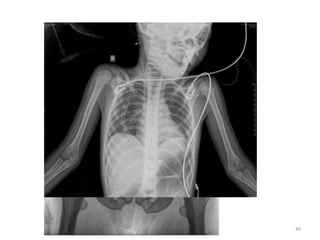

No OC has appeared (< 1 year)

No OC hasappeared (< 1 year) 37